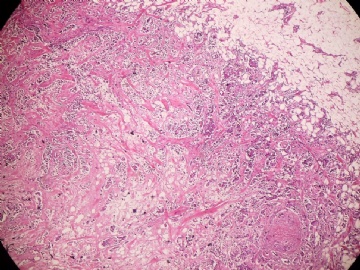

姓    名: ××× 性别:  女 年龄:  45

标本名称:  左侧近乳晕处肿物

简要病史:  患者描述有疼痛

肉眼检查:  肿物一个2.5*2*1厘米,切面灰白质地硬。

• 浸润性导管癌?图1

上皮样细胞,大部分粘附成团成巢,明显浸润。大部分细胞大,核级别高,少数图中见松散的小细胞。未见原位癌。

大细胞考虑浸润性导管癌(3级),小细胞要排除小叶癌。如果有条件请做免疫组化。

Most likely it is INVASIVE DUCTAL CARCINOMA.

DO ER/PR/HER2 STAINS

应该是浸润性导管癌,标本可能有部分自溶现象。